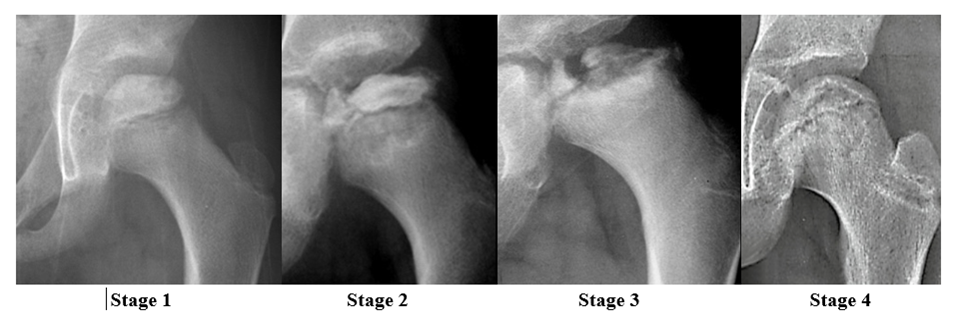

There are several classifications systems used to classify the stages of LCPD; however, this paper will use the Waldentrom classification, which refers to the associated radiographic findings for each stage. The initial stage (stage 1) results from infarction, which produces a smaller and sclerotic epiphysis with medial joint space widening. This stage may be radiographically occult for 3-6 months. The fragmentation stage (stage 2) typically begins with a subchondral lucent line (crescent sign) and then progresses to fragmentation and resorption of bone, resulting in femoral head collapse and patchy sclerotic density. The re-ossification stage (stage 3) occurs as the ossific nucleus undergoes re-ossification in which the necrotic bone is resorbed and new bone replaces. The healing or remodeling stage (stage 4) consists of femoral head remodeling until skeletal maturity. Once fully healed, the remodeled hip has the classic coxa plana, coxa magna, and “sagging rope sign” radiographic features. Dependent upon proper treatment and other patient variables, the degree of resultant deformity will vary amongst patients.